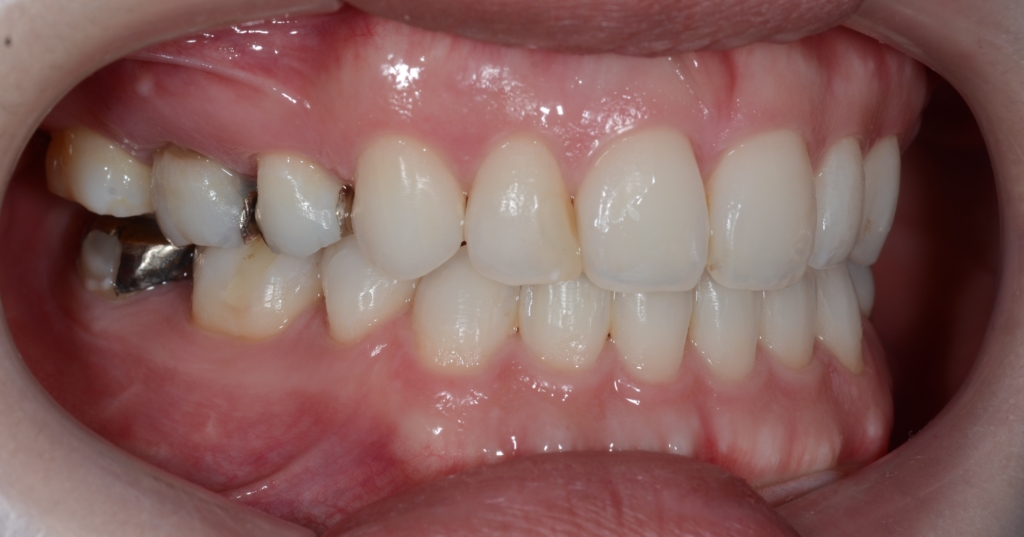

【After】

横顔や口元は患者さんの希望通りにスッキリして、満足してもらえました。

術前も口元にEラインを引くことが出来ました(レントゲン参照)が、お顔全体のバランスという意味で、同じEラインであっても術前と術後ではスッキリ感が異なります。

最後に、矯正治療前後のと「口元の写真」「レントゲン写真」「歯並び」の比較をお見せしましょう。

この方の場合、美容外科にてオトガイ形成術の既往がありました。 そのためお顔のバランスを考えた時に前歯の引っ込め具合をちょっと加減しました。 それが無ければ、もっと積極的に前歯を引っ込めて(いわゆる)顎を作るプランを実行したと思われます。